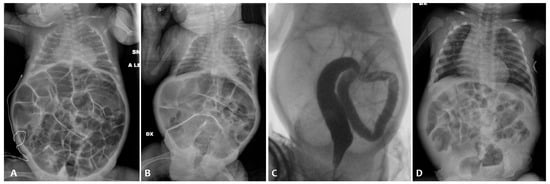

At admission (weight 650 g), an abdominal X-ray (AXR) confirmed the presence of a diffuse dilated bowel with no evidence of intra-abdominal free air (Figure 1A), and an abdominal ultrasound revealed no signs of pneumatosis. Relevant abdominal distention persisted at AXR for the next 15 days despite enteral fasting; during this period, there was no spontaneous stool production. A contrast enema was performed on day 26 using the nonionic dimer contrast agent iodixanol 320 (Visipaque), and it showed a diffuse reduction in colon caliber with multiple fecal residues (Figure 1B).

Thus, the patient received a 15-day course of NAC by nasogastric tube (twice a day) and rectal enemas (once daily). This treatment protocol resulted in an increase in mean daily stool frequency and consistency. AXR findings before and after the NAC treatment course are shown in Figure 1C,D.

Figure 1. Abdominal X-ray of patient P1 on the 10th day of life (A); contrast enema performed on the 26th day of life (B); abdominal X-ray before the NAC treatment (C) and after the NAC treatment (D).